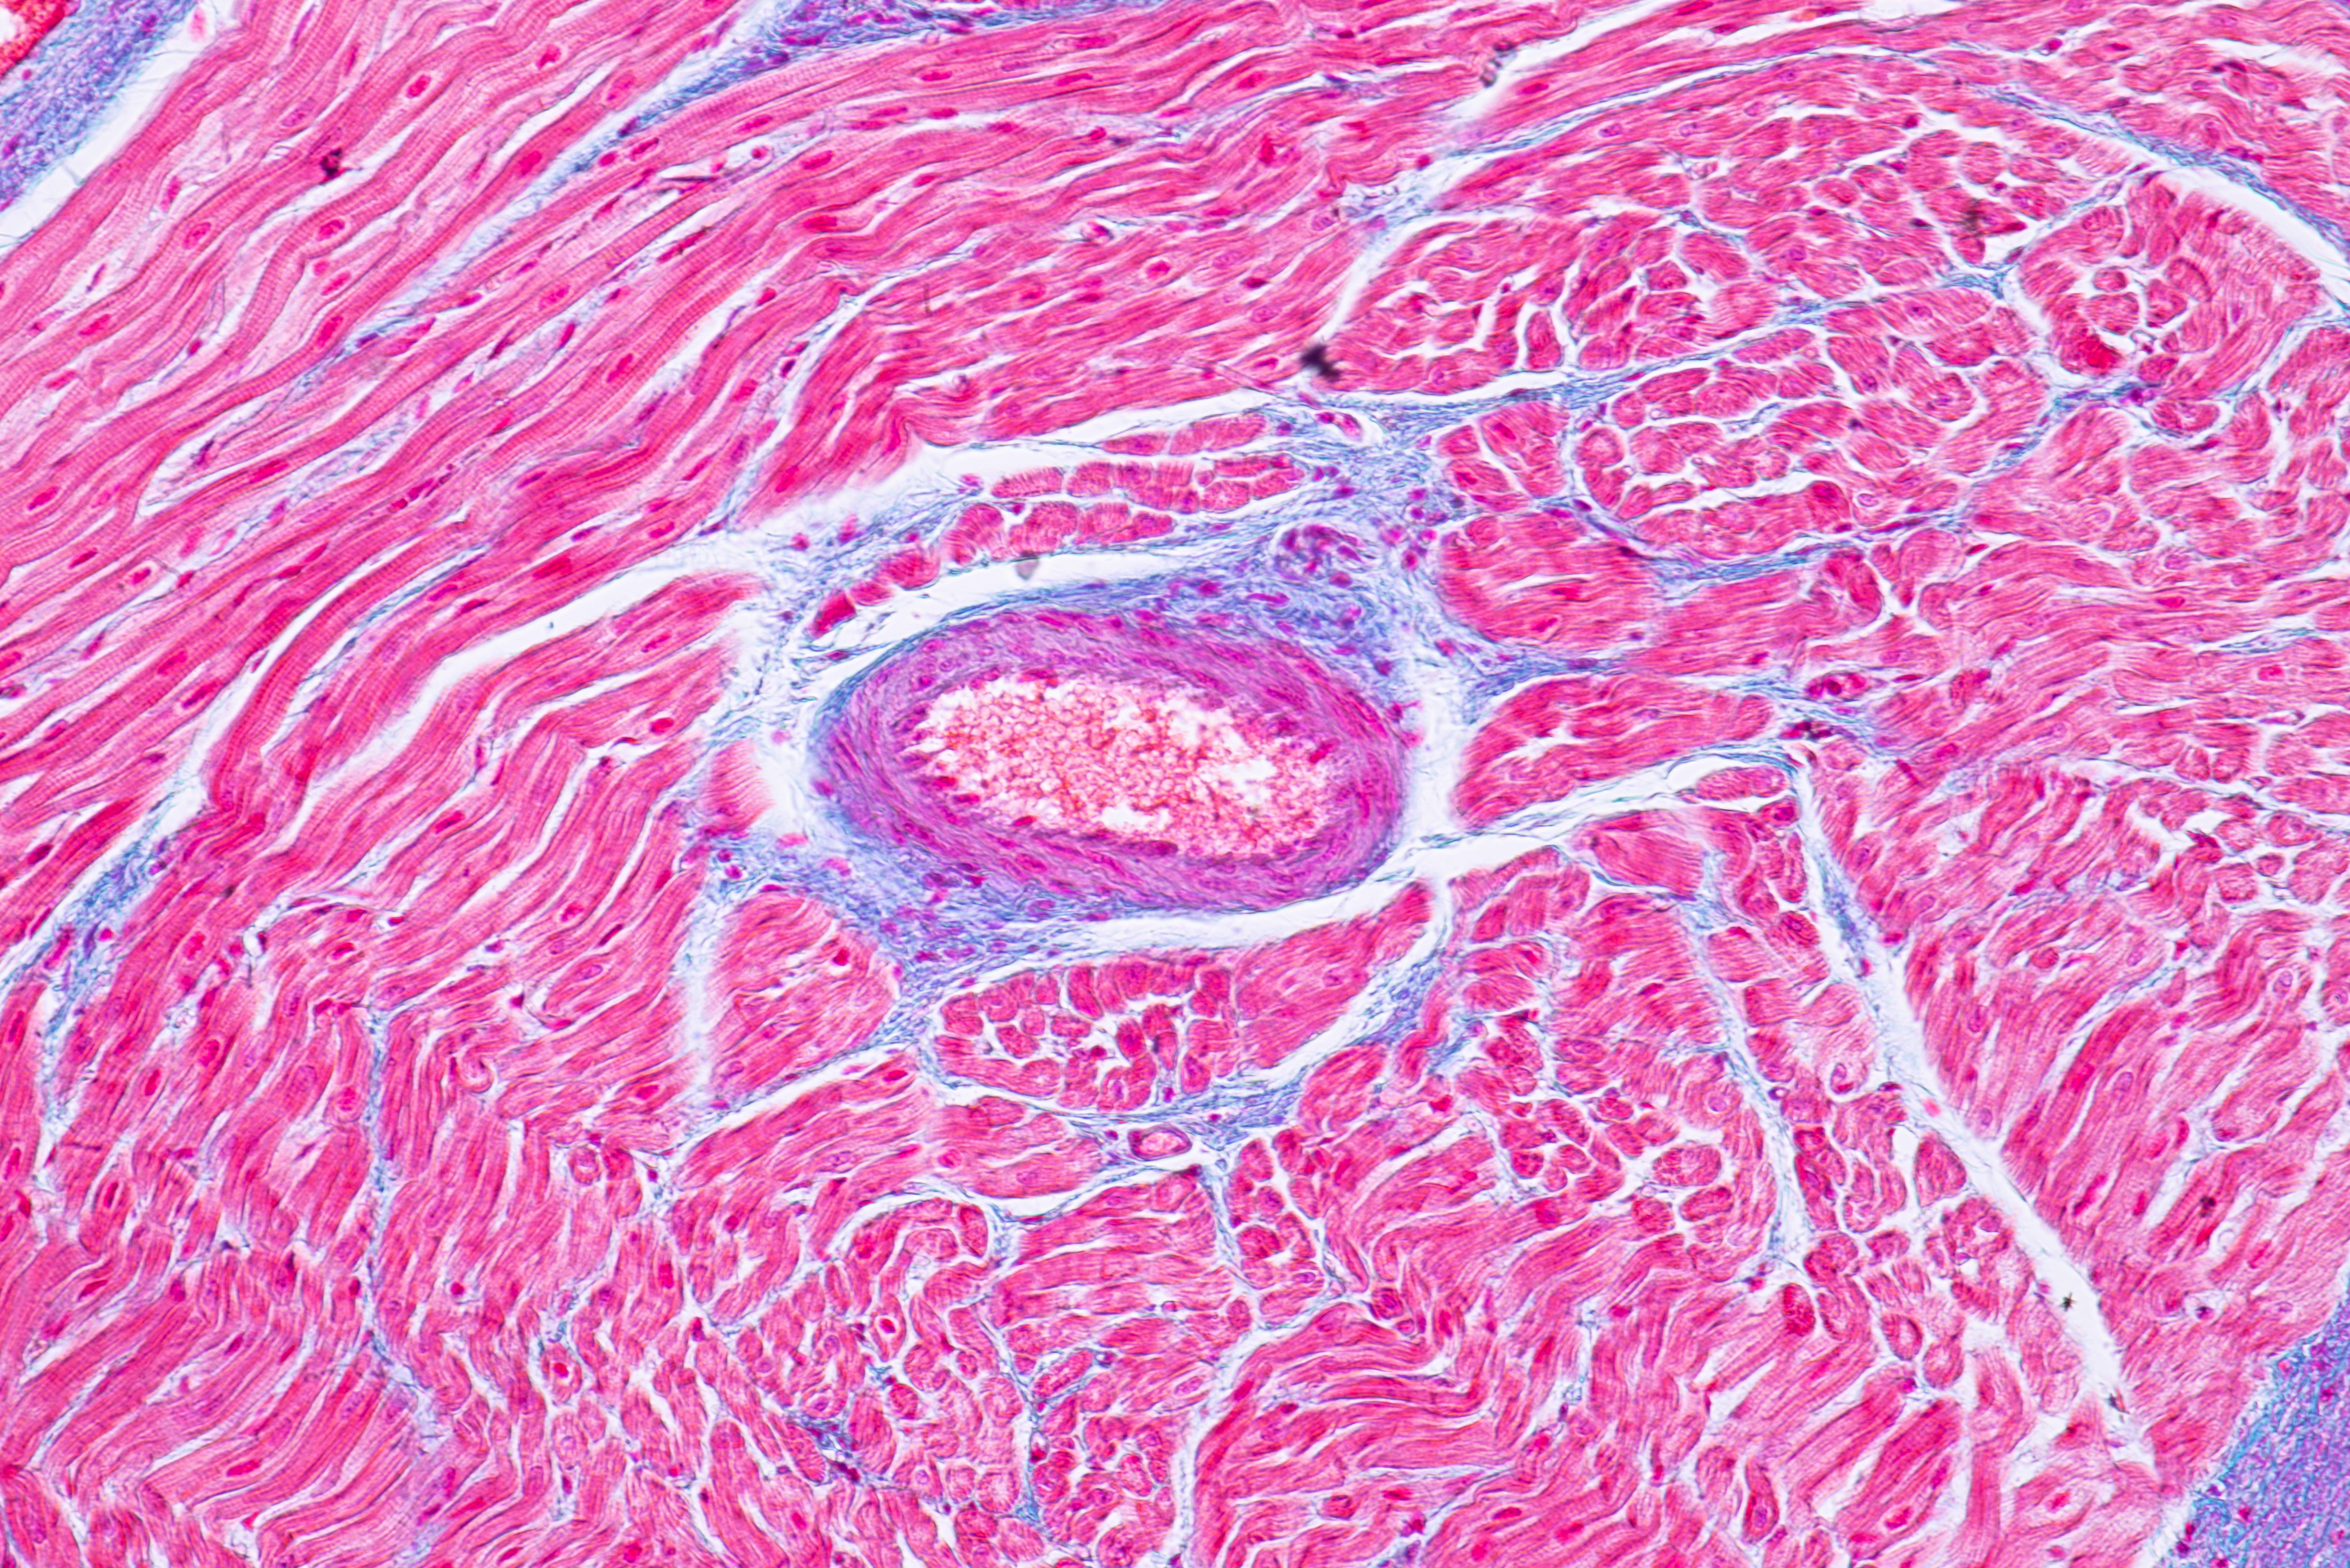

Ces chercheurs du Texas A&M décryptent un peu plus les effets nocifs des boissons énergisantes sur le cœur. Ils montrent, dans la revue Food and Chemical Toxicology, comment ces boissons peuvent parfois « donner un coup de pouce », mais dans d’autres cas, contribuer au développement de maladies cardiaques graves. En cause, des effets directs sur les cardiomyocytes, les cellules musculaires du cœur.

La consommation de ces boissons a en effet déjà été associée à l’arythmie et à la tachycardie ainsi qu’à la cardiomyopathie (une maladie du muscle cardiaque qui rend difficile le pompage du sang par le cœur), à une augmentation de la pression artérielle et à d'autres anomalies de la fonction cardiaque. Ici, l’équipe observe in vitro que les cardiomyocytes cultivés en laboratoire et exposés à certaines boissons énergisantes, présentent une augmentation du rythme cardiaque et d'autres facteurs de risque cardiaque.

Les recherches vont se poursuivre sur les ingrédients identifiés pour préciser les doses maximum tolérables, en particulier chez les consommateurs à antécédents cardiovasculaires. Cependant cette première phase in vitro confirme des effets observables et significatifs sur les cardiomyocytes humains.